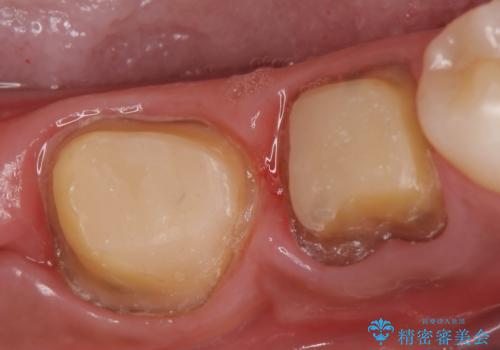

- 奥歯が欠けてしまったので診て欲しいといらっしゃった方の症例です。

再根管治療終了後、オールセラミッククラウンによる補綴を行いました。

- オールセラミッククラウン…¥100,000×2、仮歯…¥10,000×2、ファイバーコア…¥20,000×2費用は治療当時の料金となります